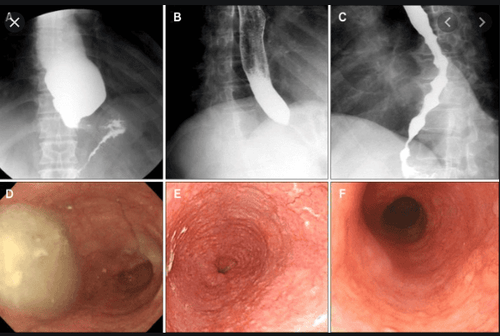

Phương pháp điều trị nội soi mới nhất cho chứng achalasia và các rối loạn vận động thực quản liên quan là phẫu thuật mở cơ qua nội soi qua đường miệng (POEM). Bốn bước với POEM bao gồm: 1) rạch niêm mạc của thành thực quản; 2) tạo đường hầm dưới niêm mạc đến phần trên của dạ dày; 3) cắt cơ vòng và / hoặc cơ dọc từ thực quản xa đến phía trên dạ dày và 4) đóng vết rạch niêm mạc ở thành thực quản. Các báo cáo đã chứng minh khả năng giảm khó nuốt tương đương với phẫu thuật cắt cơ Heller nhưng với thời gian hồi phục ngắn hơn, chi phí thấp hơn và giảm biến chứng tim phổi. GERD được thấy phổ biến hơn sau thủ thuật POEM, tuy nhiên vì quá trình tạo hình phình vị không được thực hiện sau phẫu thuật cắt bỏ cơ. Các thử nghiệm ngẫu nhiên so sánh POEM với Heller myotomy đang được tiến hành.

Thủ thuật POEM – mở cơ qua nội soi đường miệng điều trị co thắt tâm vị